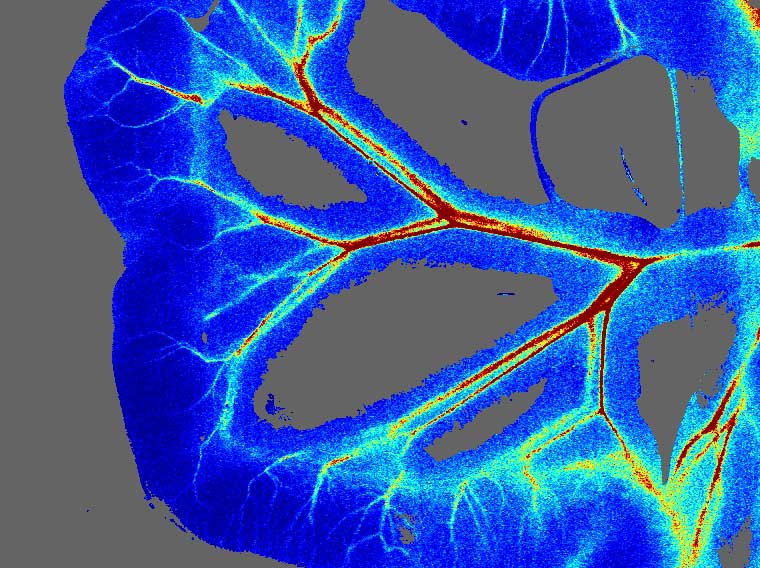

腸系膜循環(huán)系統是機體最大的血管床之一,與全身循環(huán)密切相關(guān)。腸系膜循環(huán)的調節機制不但對臟器局部有影響,對全身循環(huán)亦有影響。使用激光多普勒血流成像系統,可有效觀(guān)察腸系膜的微循環(huán)狀態(tài),并對微循環(huán)狀態(tài)進(jìn)行量化。

腸系膜血流成像

moorLDI激光多普勒血流成像                                                        moorFLPI-2激光散斑血流成像